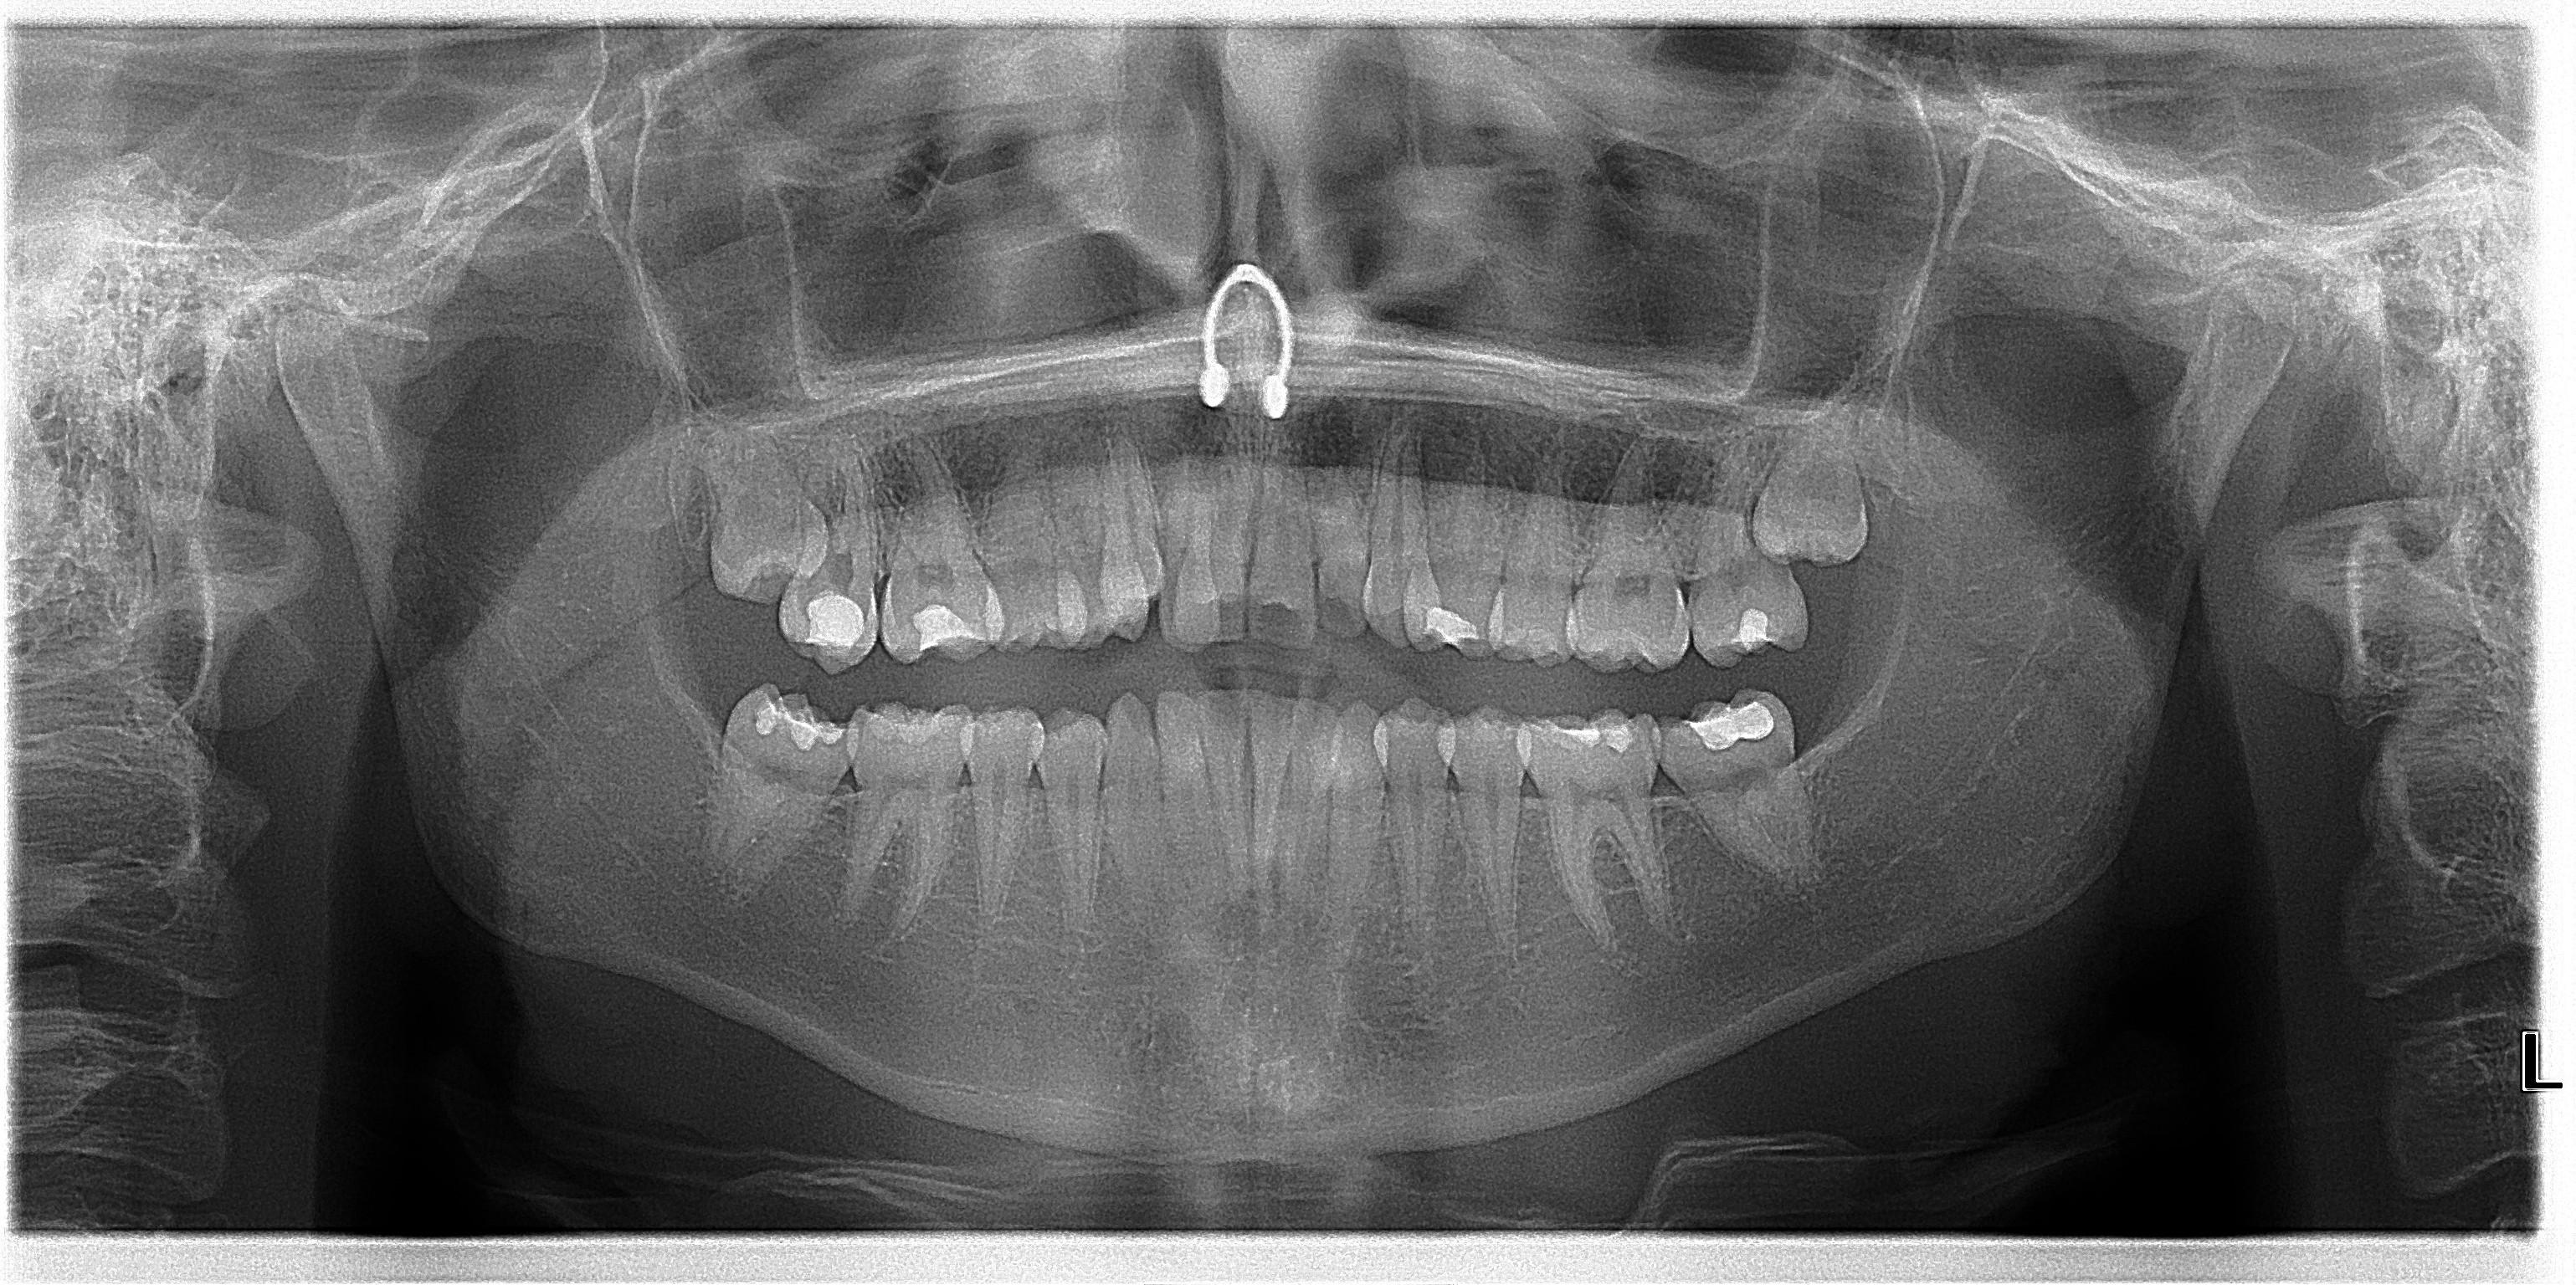

18 & 28 exo - Under Moderate Sedation

38 exo -Under Moderate Sedation

37 exo - Under Moderate Sedation